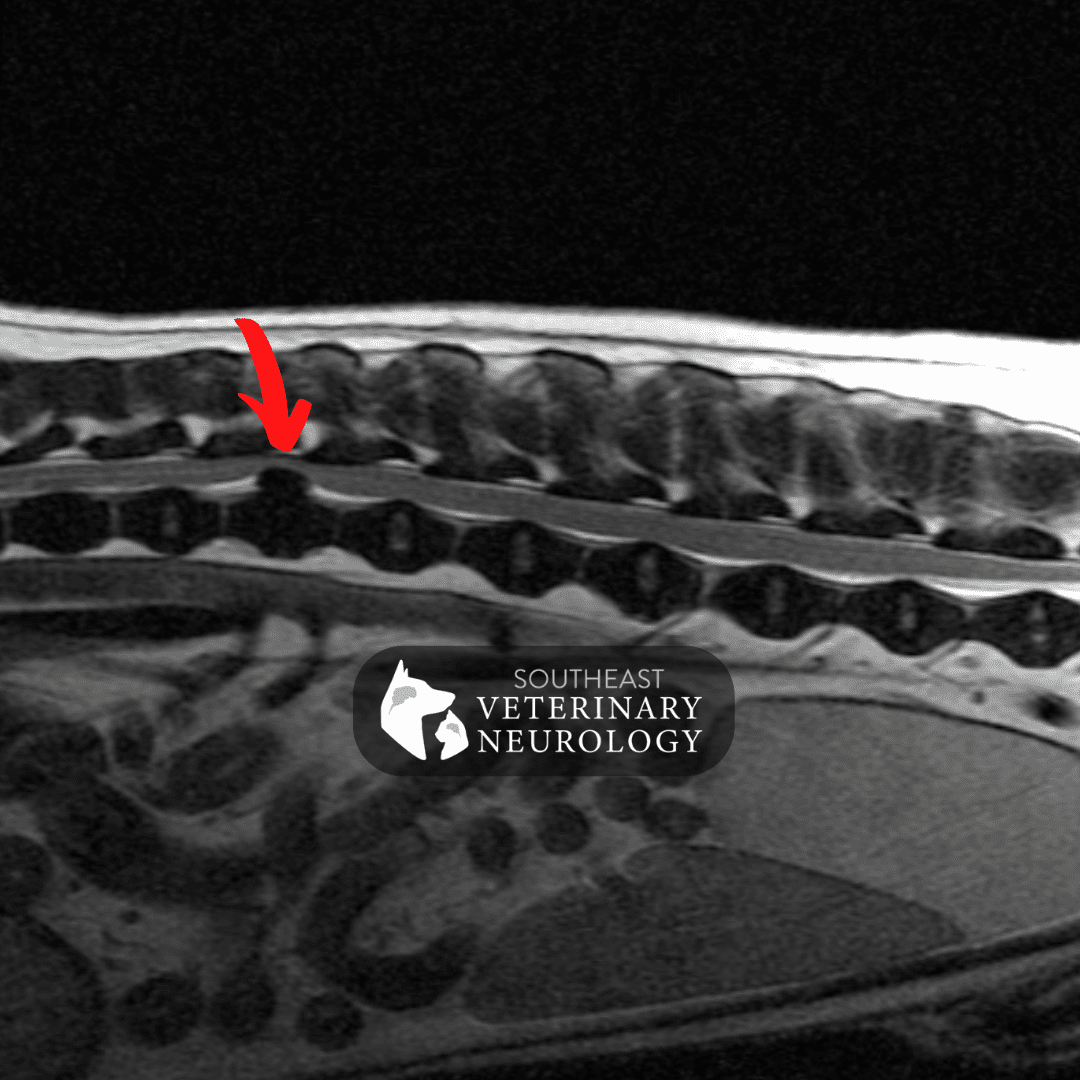

From sevneurology.com

Dog Herniated Disc Signs and What to Do Southeast Veterinary Neurology Slipped Disk In Dogs intervertebral disc disease is a severe health condition in dogs that requires immediate medical attention. intervertebral disc disease (ivdd) in dogs is a neurologic condition affecting the spinal cord. Here are some warnings that. Here are some signs that your dog needs prompt veterinary attention:. It can range in severity, from pain to paralysis. Just as in your. Slipped Disk In Dogs.